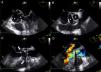

One month later, the patient presented again in the emergency department complaining of abdominal pain and persistent asthenia and fatigue. An abdominal computed tomography scan showed a large splenic mass and an exploratory laparotomy was performed. Intraoperatively, an extensive abscess was noted which extended to the diaphragm and ipsilateral pleural cavity. The spleen was removed and the material collected for microbiological analysis. Given this setting, and to exclude potential embolic sources, echocardiographic assessment was repeated. The transesophageal echocardiogram showed multiple abscesses (Figure 2A, asterisk) surrounding the single-disc mechanical aortic prosthesis (Figure 2A, cross). There appeared to be no communication between the abscesses and the cardiac cavities, thus excluding the possibility of a pseudoaneurysm (Figure 2B, white arrow) and there were no signs of prosthetic dysfunction. The patient began appropriate antibiotic therapy and was referred for surgery.

Transesophageal echocardiogram in mid-esophageal short- (A) and long-axis (B) views of the aortic prosthesis, showing two abscesses (A, asterisk) surrounding the single-disc mechanical prosthetic valve (A, cross). There appears to be no rupture from these abscesses (B, white arrow) to the left ventricular outflow tract.